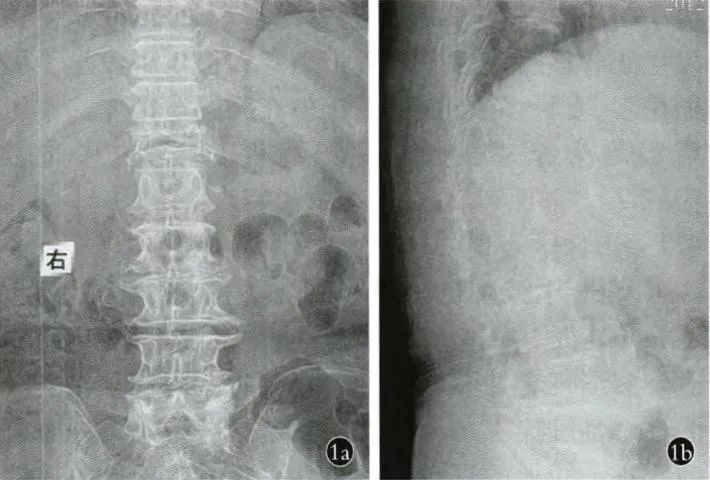

X线片或CT扫描可见真空裂隙征(IVC)或空壳样改变及骨不连(假关节)。站立位椎体高度丢失及后凸畸形明显,卧位CT及MRI检查时,椎体矢状位提示椎体高度基本恢复(图1),这种动态性变化提示椎体骨不连(或假关节)存在。

图1a,b 正侧位X线片示T12:椎体内横形透亮线,呈裂隙样改变。